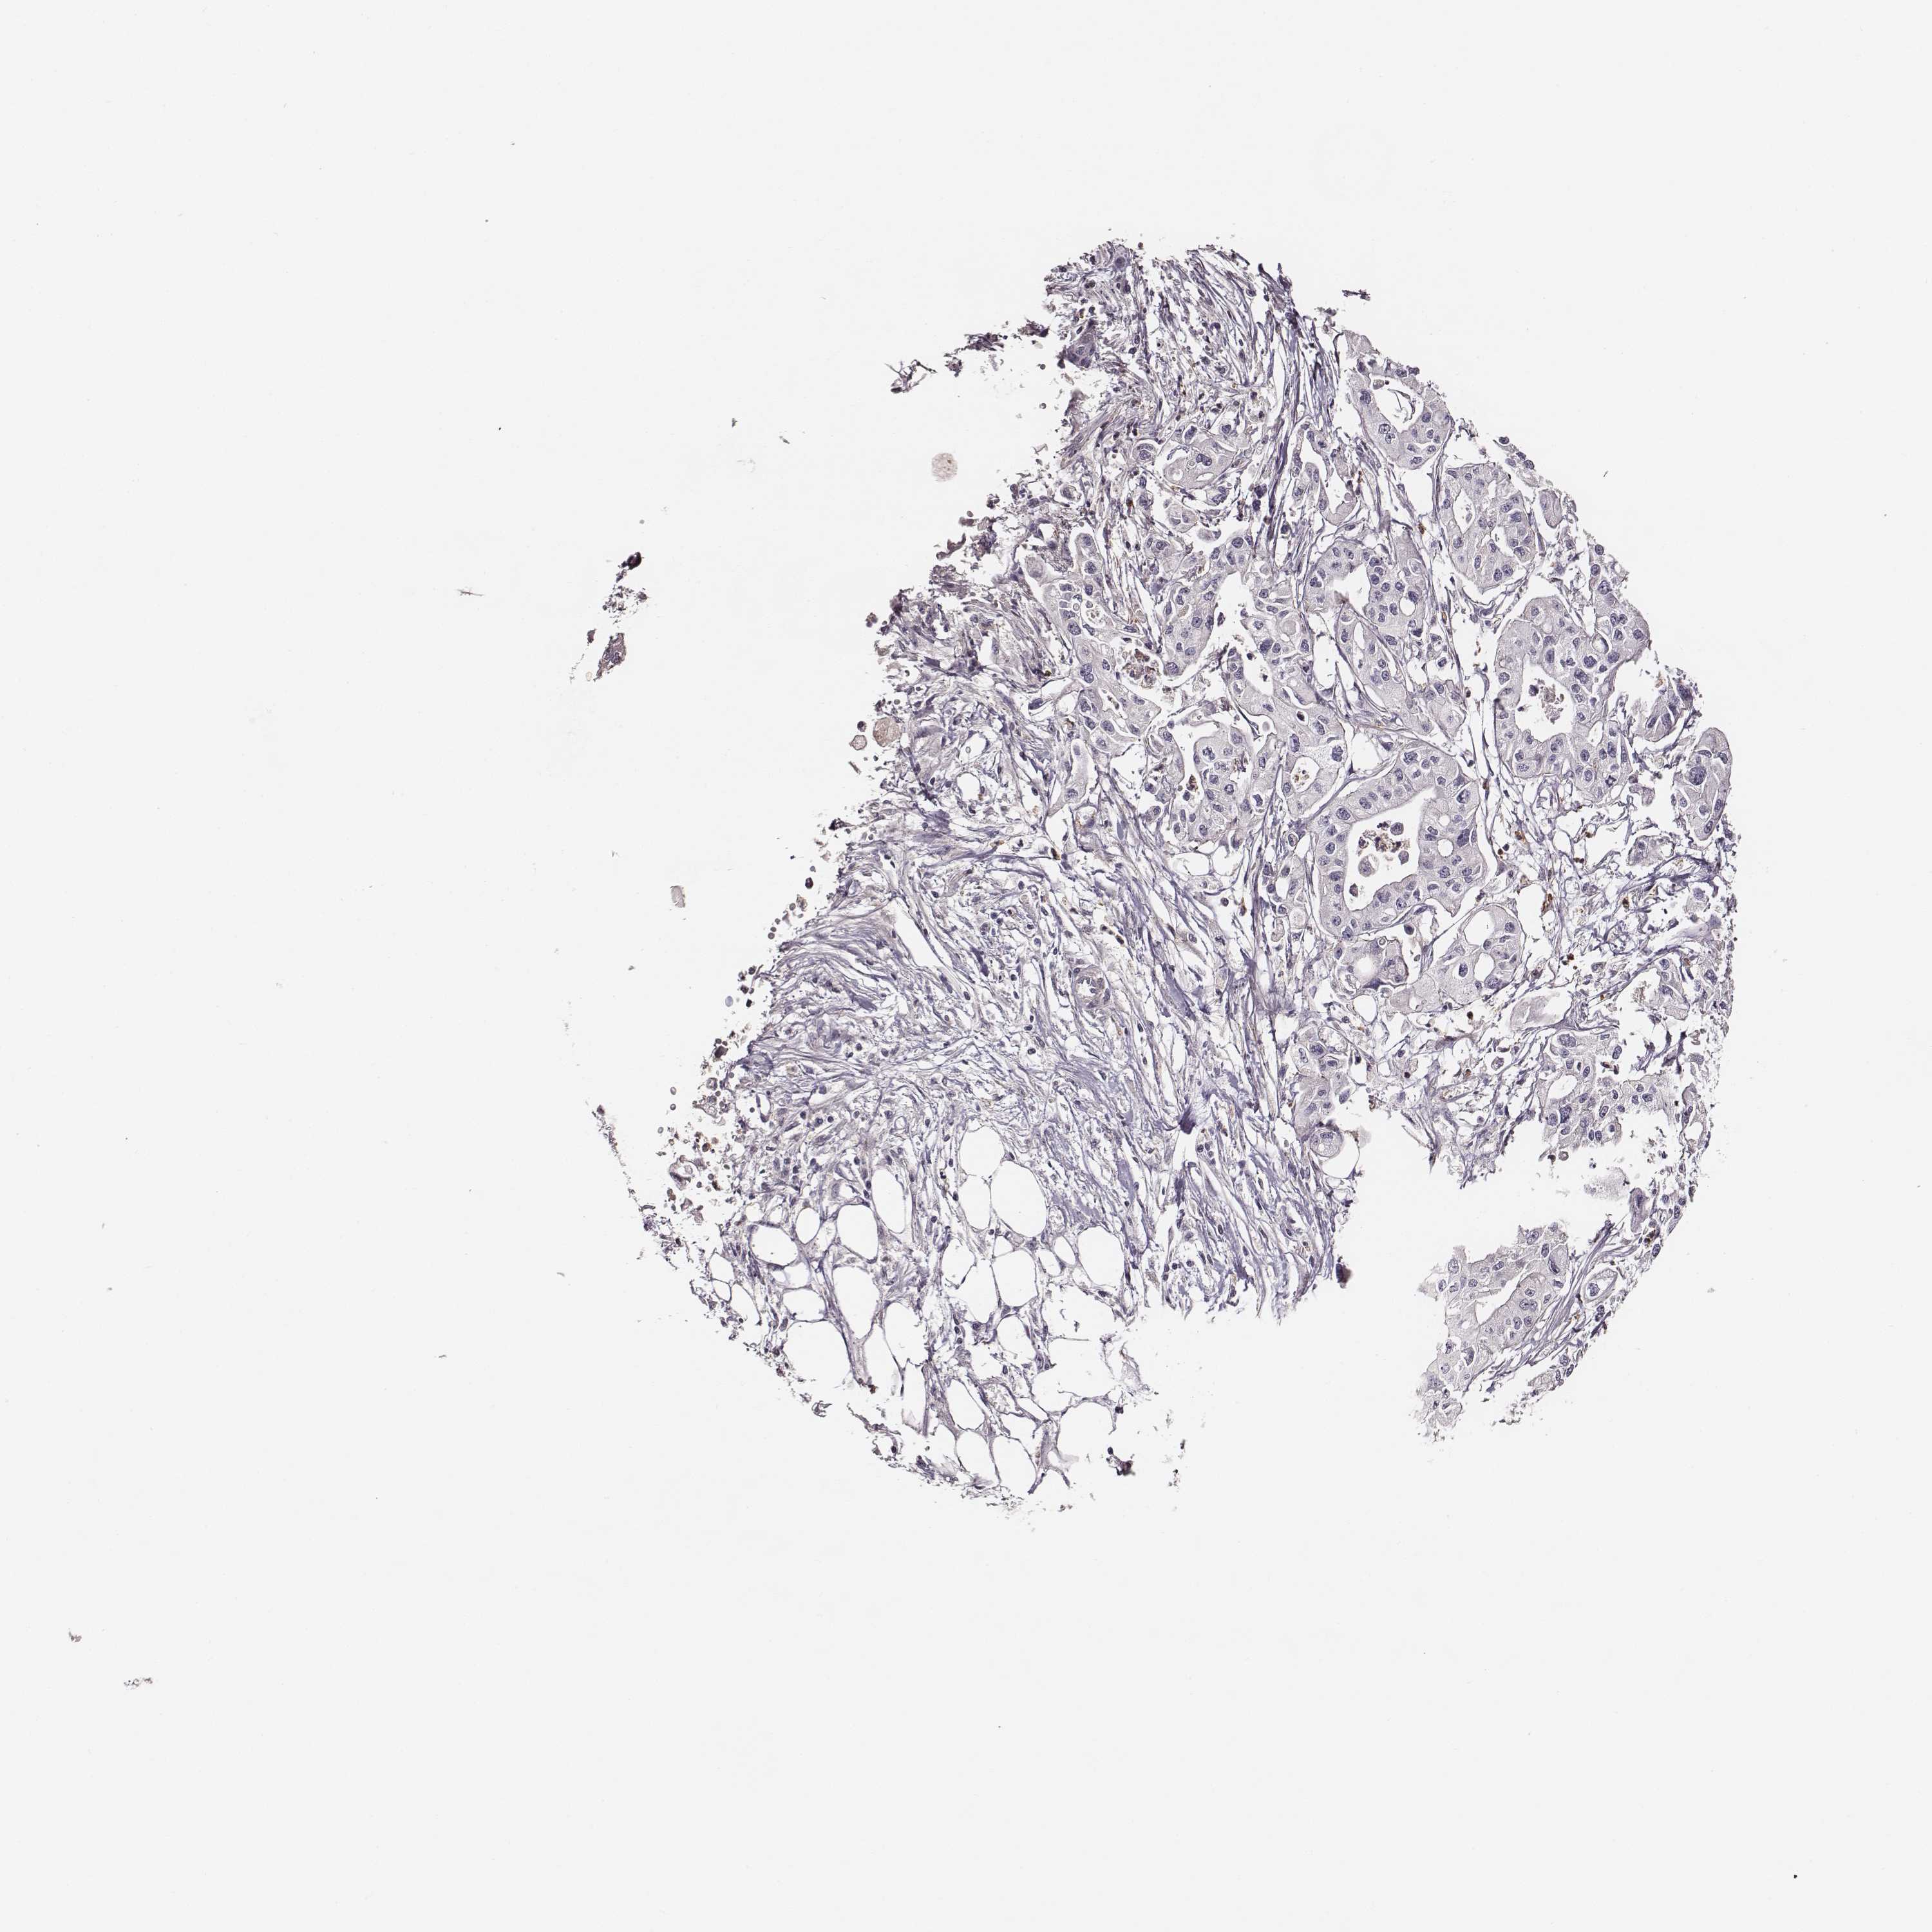

PANCREATIC CANCER - Protein expressioni

A mouse-over function shows sample information and annotation data. Click on an image to view it in a full screen mode. Samples can be filtered based on level of antibody staining by selecting one or several of the following categories: high, medium, low and not detected. The assay and annotation is described here.

Note that samples used for immunohistochemistry by the Human Protein Atlas do not correspond to samples in the TCGA dataset.

Antibody stainingi

Antibody staining in the annotated cell types in the current human tissue is reported as not detected, low, medium, or high, based on conventional immunohistochemistry profiling in selected tissues. This score is based on the combination of the staining intensity and fraction of stained cells.

Each image is clickable and will lead to virtual microscopy that enables deeper exploration of all samples and also displays staining intensity scores, fraction scores and subcellular localization as well as patient and tissue information for each sample.

Antibody HPA004835

Antibody HPA073497

Antibody CAB009321

Antibody CAB075747

Adenocarcinoma, NOS